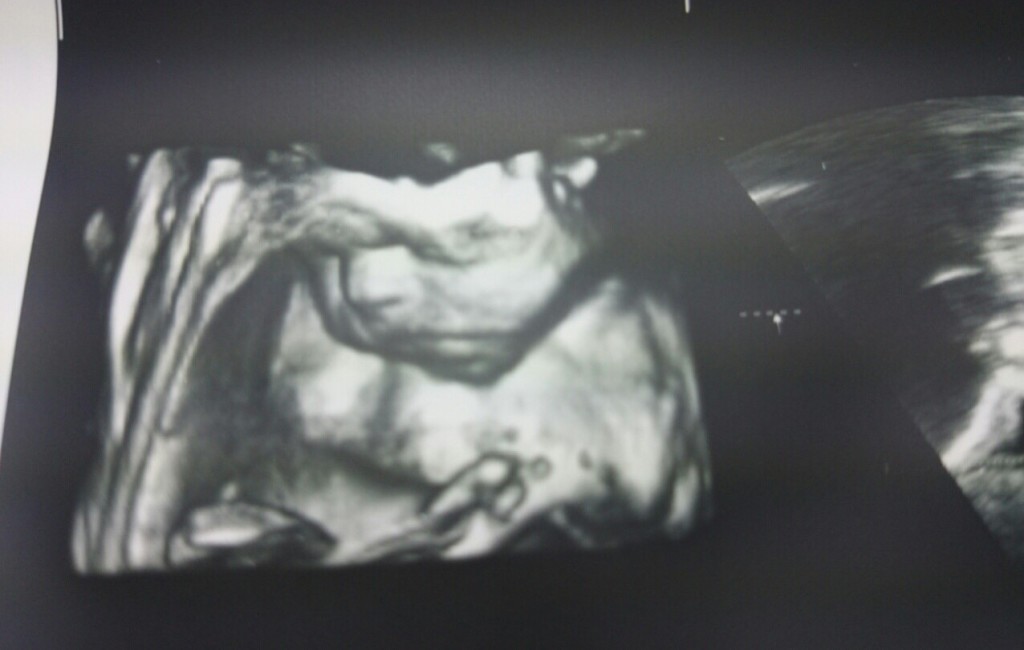

Dužina bebice je oko 30 centimetra od tjemena do pete. Težina iznosi oko 600 grama.

Razvoj fetusa je više-manje završen. Zatvorene oči su na prednjoj strani lica, a uške točno pozicionirane.

Razvijene su trepavice, a raste i kosa. Vaša beba izgleda gotovo kao novorođenče. S rastom bebe kretnje postaju ograničene. Ona je svjesna svog okruženja i ako doživite kakav šok i vaša će se beba prestrašiti.